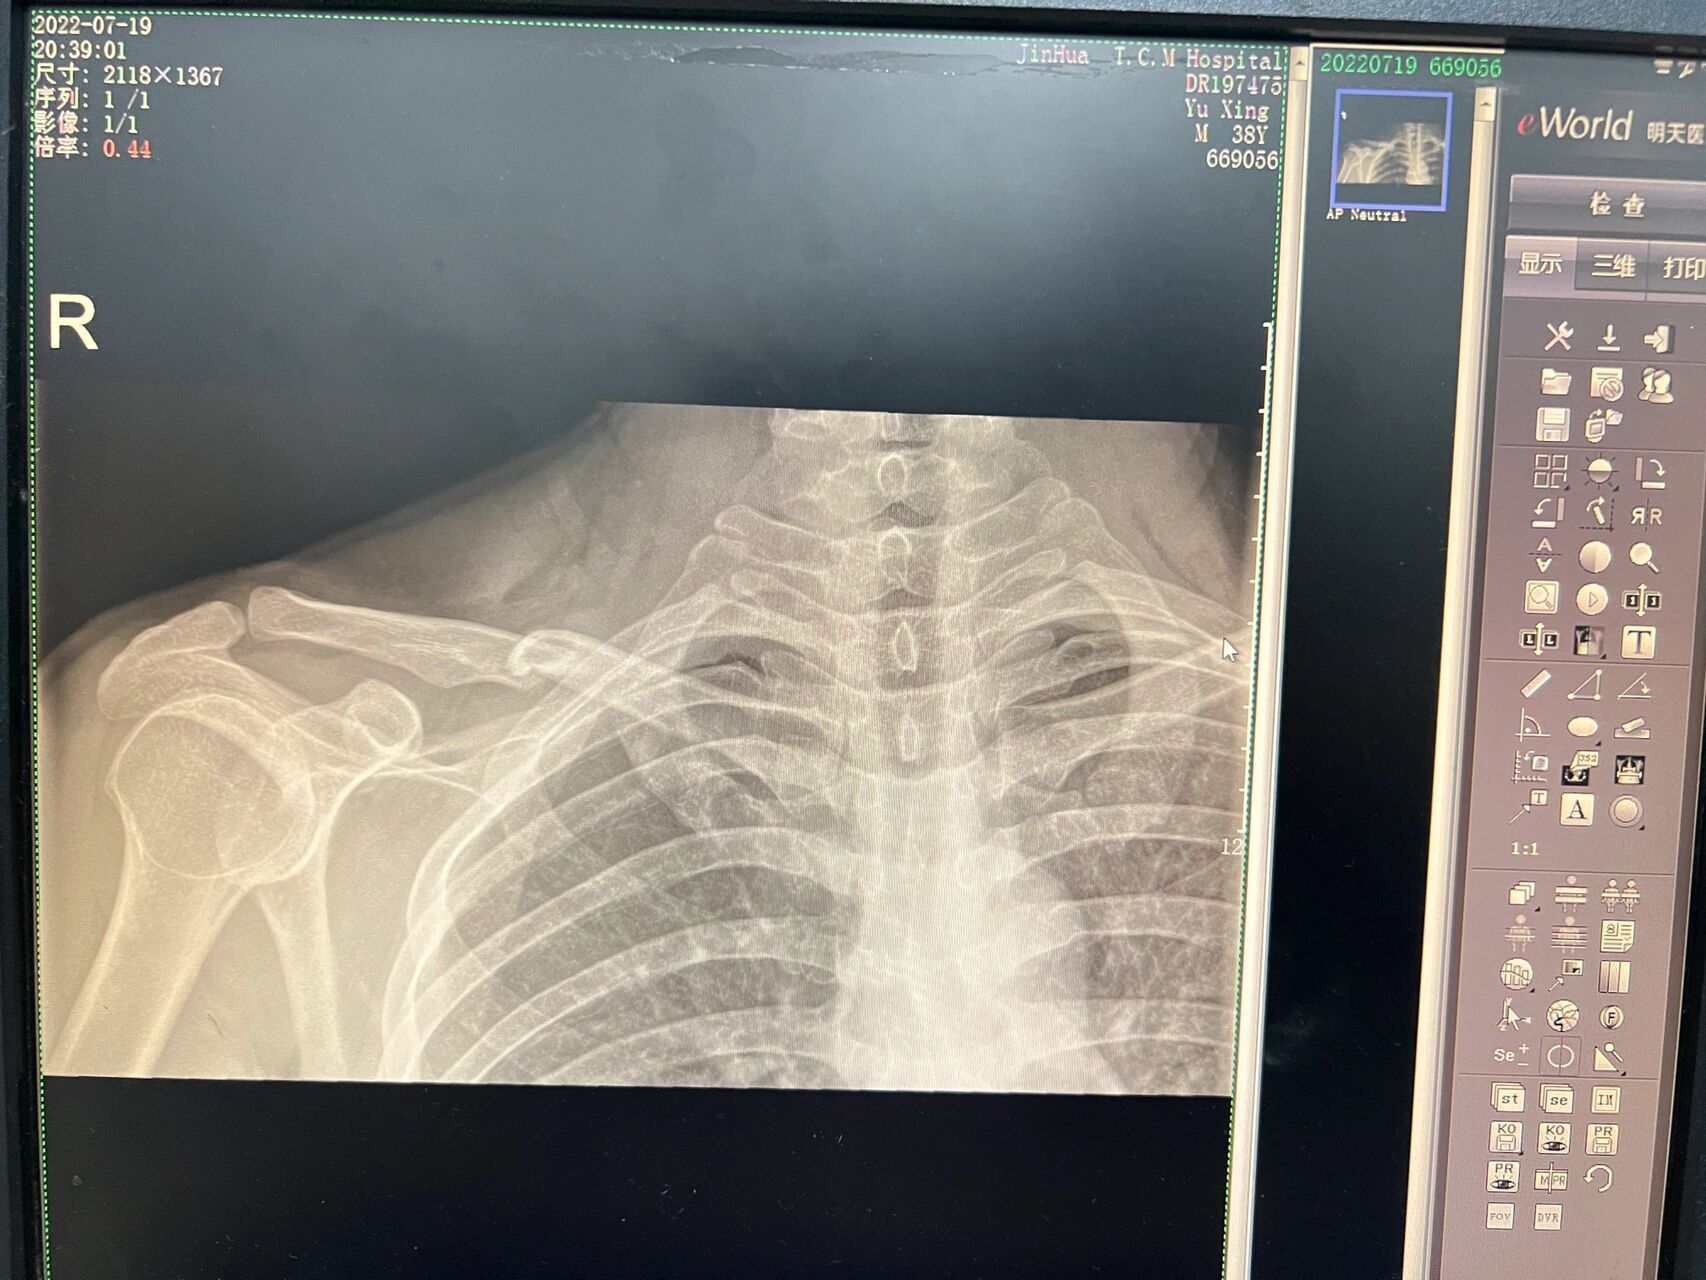

患者双侧锁骨摄片